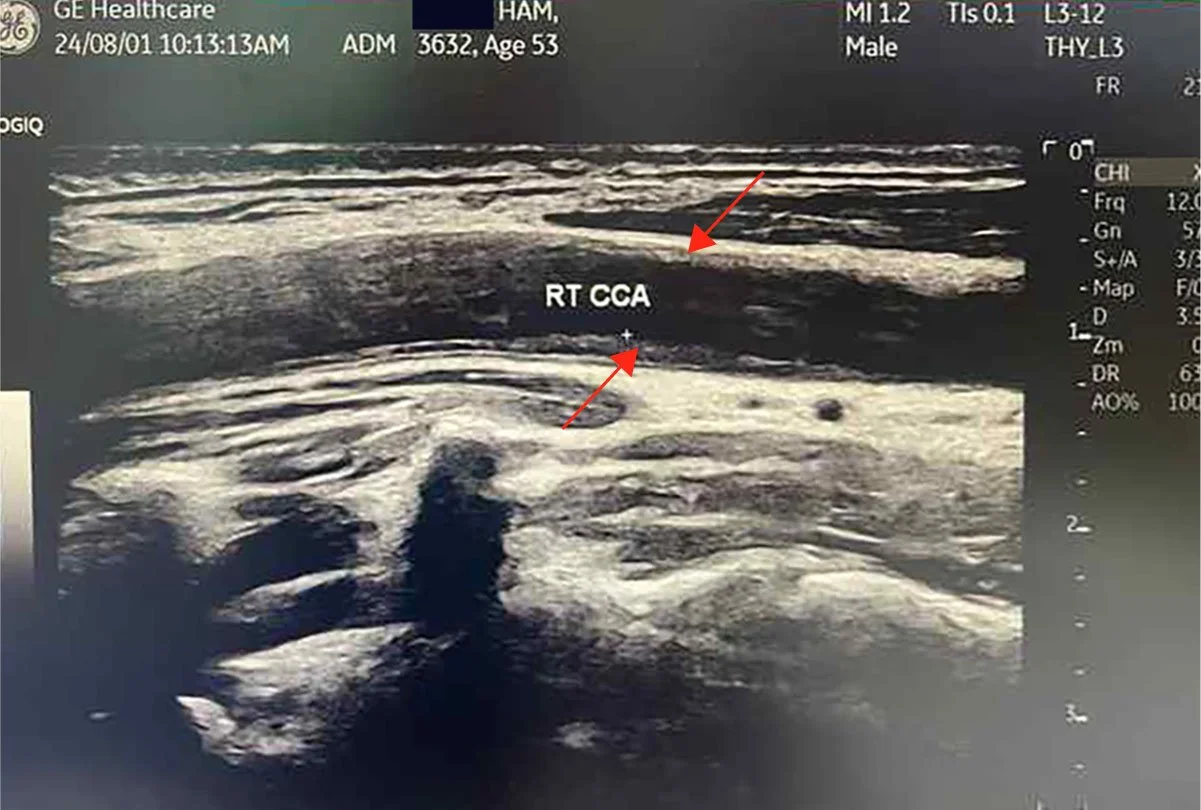

I thought about this when I looked at my carotid images. What I had inside my arterial wall was not soft tissue. It was plaque that had hardened, visible on ultrasound, that a close physician friend described as among the worst he had seen in a 55-year-old man. When the arterial wall becomes rock, the blood cannot flow freely. The organs that depend on that flow begin to fail. The water of life is inside you. The question is whether the rock will yield it. Mine did.

And here is what reversal looks like. My carotid plaque. Gone. Remodeled. In three months. Bilateral carotid IMT of 1.8 mm and 1.6 mm with visible plaque on both sides, dropping to 0.84 mm and 0.86 mm with no visible plaque detectable on ultrasound. My CT-FFR on a dominant D1 diagonal with 77 percent stenosis: improved from 0.75 to 0.80, crossing from ischemic into the normal range. LDL: 61, a 64 percent reduction. ApoB: 45. The word my physician friends used: Unbelievable!

Before: RT CCA . Longitudinal . Baseline

After: Plaque remodeling and reversal. B-mode ultrasound imaging of the carotid artery. Kevin Ham, MD, 2025. Three months on the CAST protocol: WFPB diet, high-intensity cycling, structured fasting, targeted supplementation.